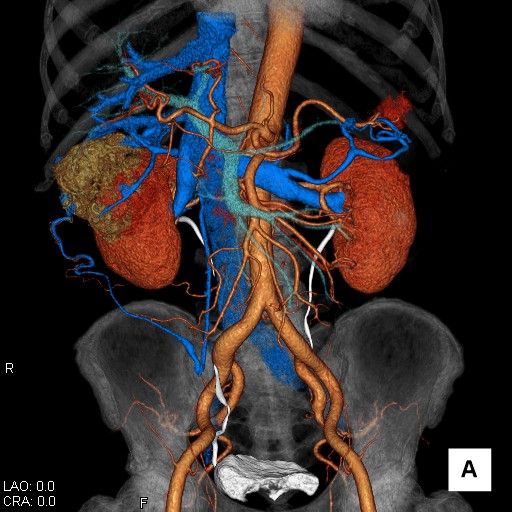

CT検査はがん診療において様々な用途で行われます。

肺がんはCT検査で存在診断が可能です。肝がんなどは造影剤を使用することで病気内の血行動態を知ることができ質的診断が可能です。

また、病気周囲の血管の走行を知ることもできるため、手術の安全性を確認することができます。CT検査は短時間で広範囲に検査することができます。

肝臓造影CT検査画像(大腸がん肝臓転移)

腎臓造影CT検査 3D画像